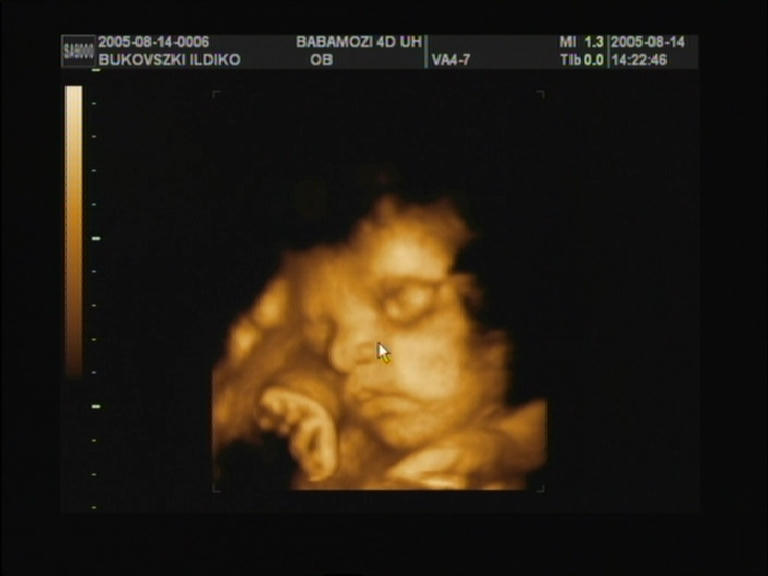

30.hét..egy kis mosollyal |